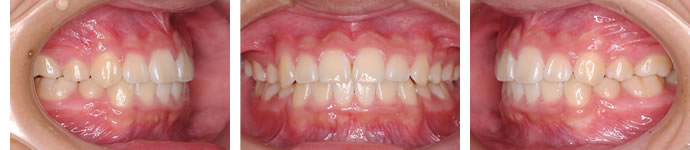

■治療後

ガタガタは改善され、理想的な歯並びと咬み合わせに仕上がっています。

無理な拡大などは一切行っていませんので、口元も出っぱりすぎることはなく調和がとれています。

動的治療期間は2年2ヶ月でした。